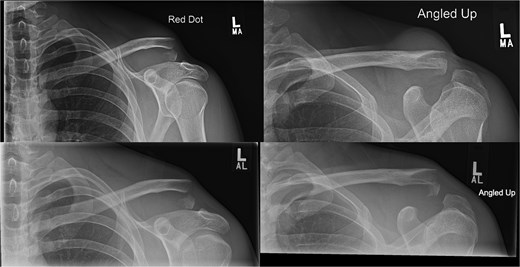

A 30-year-old male presented with an unstable lateral clavicle fracture and skin tenting after a rugby injury. Imaging revealed a Neer type IV equivalent fracture (Fig. 3). He underwent open reduction and internal fixation with coracoid exposure and TightRope placement, reinforced with fiber-wire. Postoperative recovery included sling immobilization followed by pendular exercises. Despite delayed radiological union, he achieved full range of motion and strength by three months, with only mild, asymptomatic clavicular prominence. He returned to physically demanding work without restrictions, and final imaging confirmed union (Fig. 4A–C).

Radiographs of second case showing a displaced lateral end clavicle fracture with deformity and dorsal displacement.

(A–C) Radiographs showing complete healing of the second case and union at 3, 6, and 12 months post-operatively.